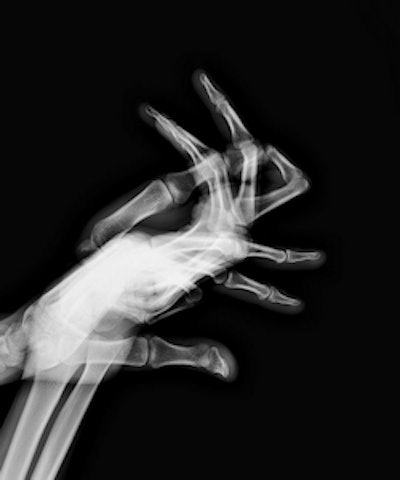

"Skin and bones" from the Hand Plays modified presence series. All images © Marc Ferrante (marcferrante.com).The impetus behind the investigation was Article L. 1333-11 of the Public Health Code, which states that ionizing radiation cannot be used on the human body for purposes other than diagnosis, treatment, or biomedical research. The penalty for infringement can range up to one year in prison and a fine of 15,000 euros, ASN noted.

The Hand Plays project is divided into six series of images. In the "object theater" series, for example, scans were taken of hands wearing a range of objects, from more traditional puppets to poultry. Other series include "skin," in which the bones are removed, leaving only an image of the skin, and "ergon," which visualizes the space between the hands.

"Rabbit" from the shadow play series.